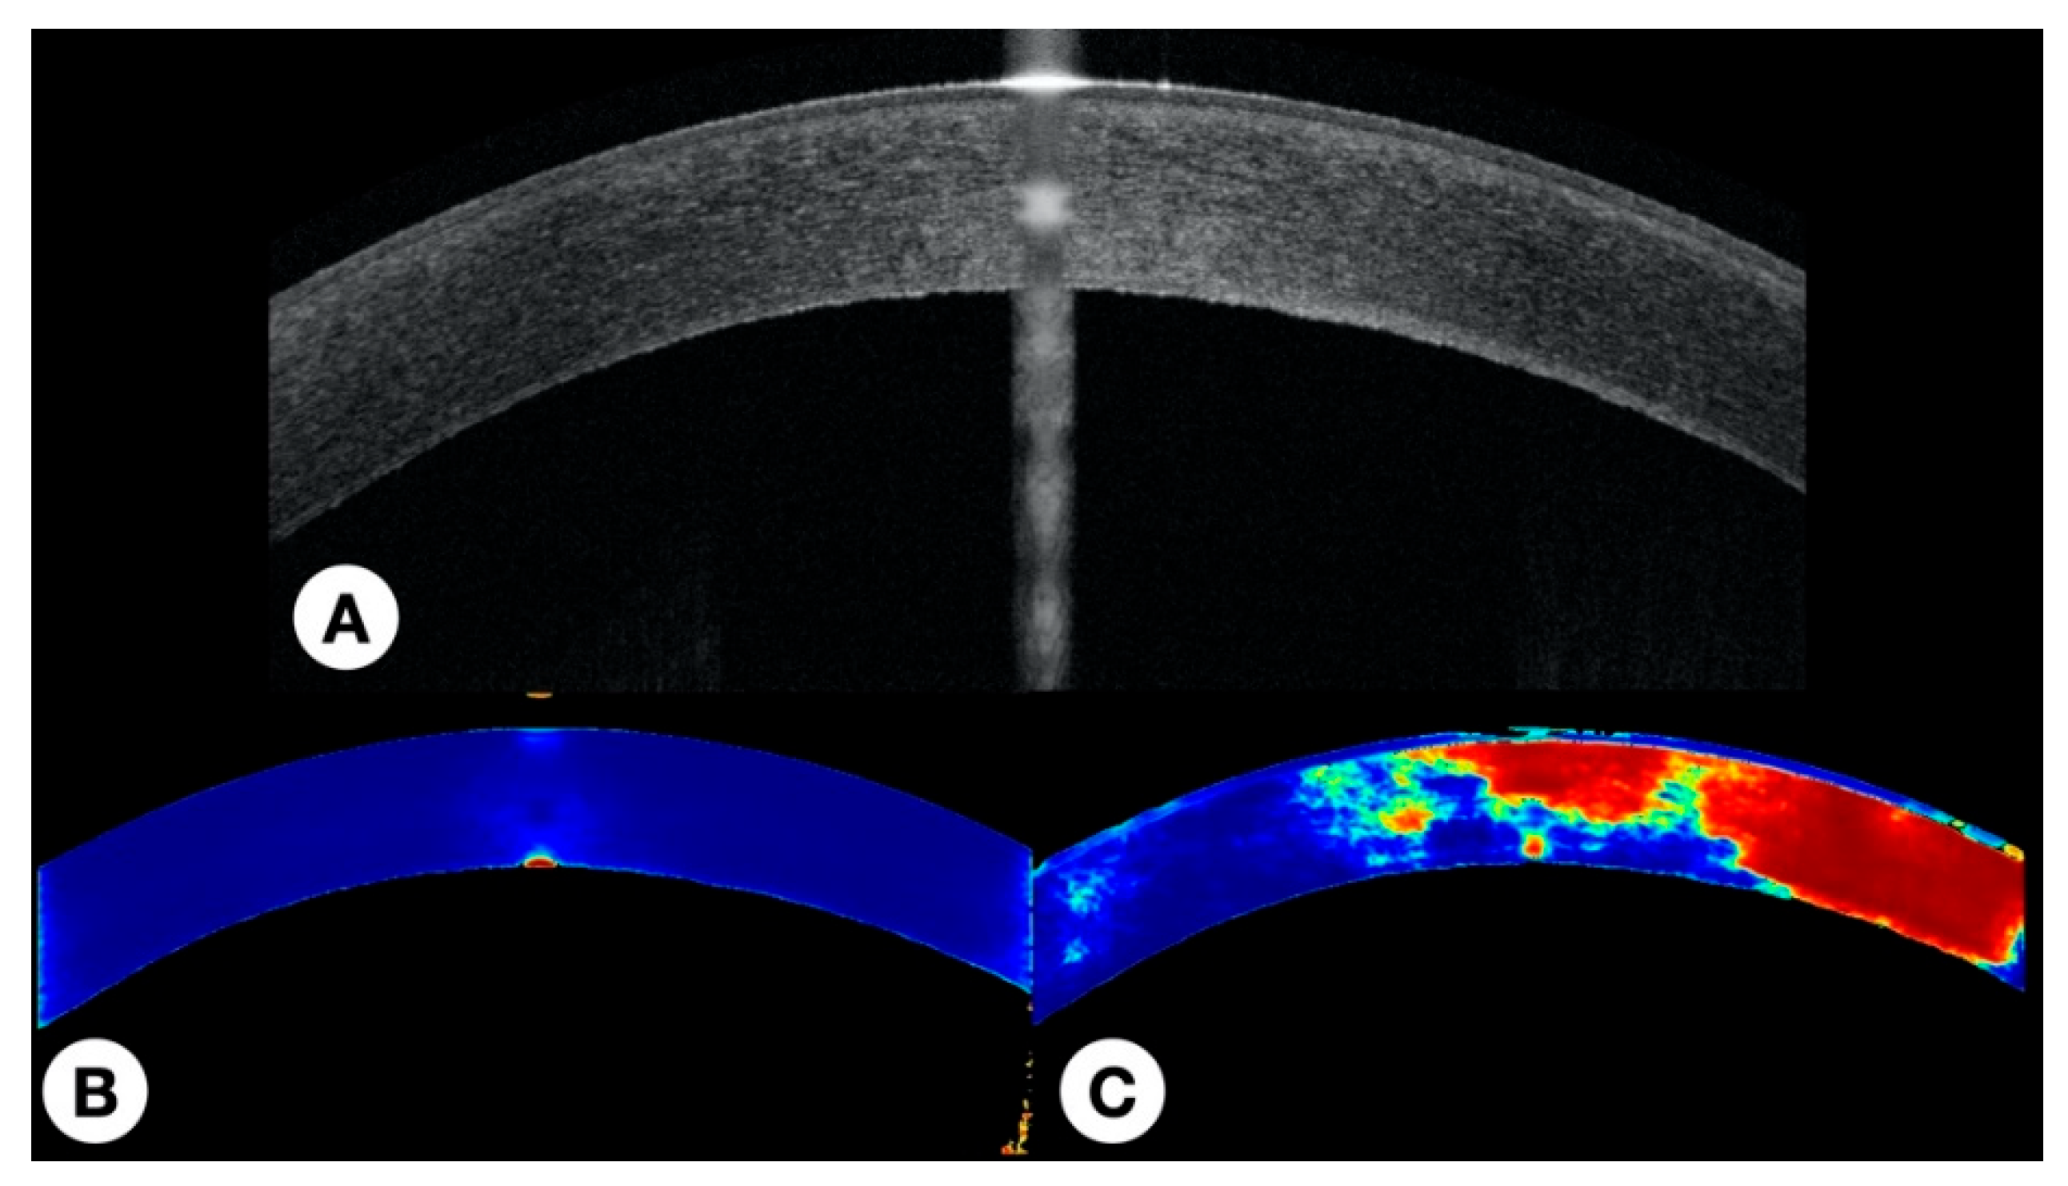

2.5.4. Visual Representation of the Results